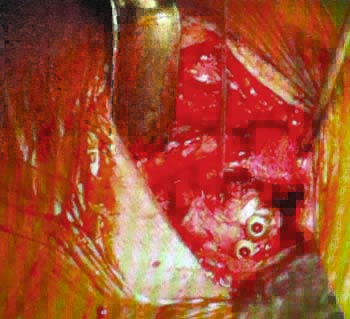

Figura 4: Cirugía de Latarjet, se observa la fijación con 2 tornillos de la coracoides y el remanente de ligamento CA preparado para reforzamiento capsular. Se observa sutura de anclaje en reborde glenoideo).